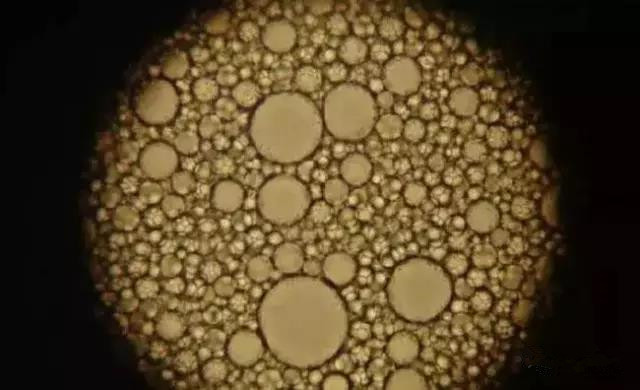

“ 镜下脂肪滴

“ 肝脂肪空泡